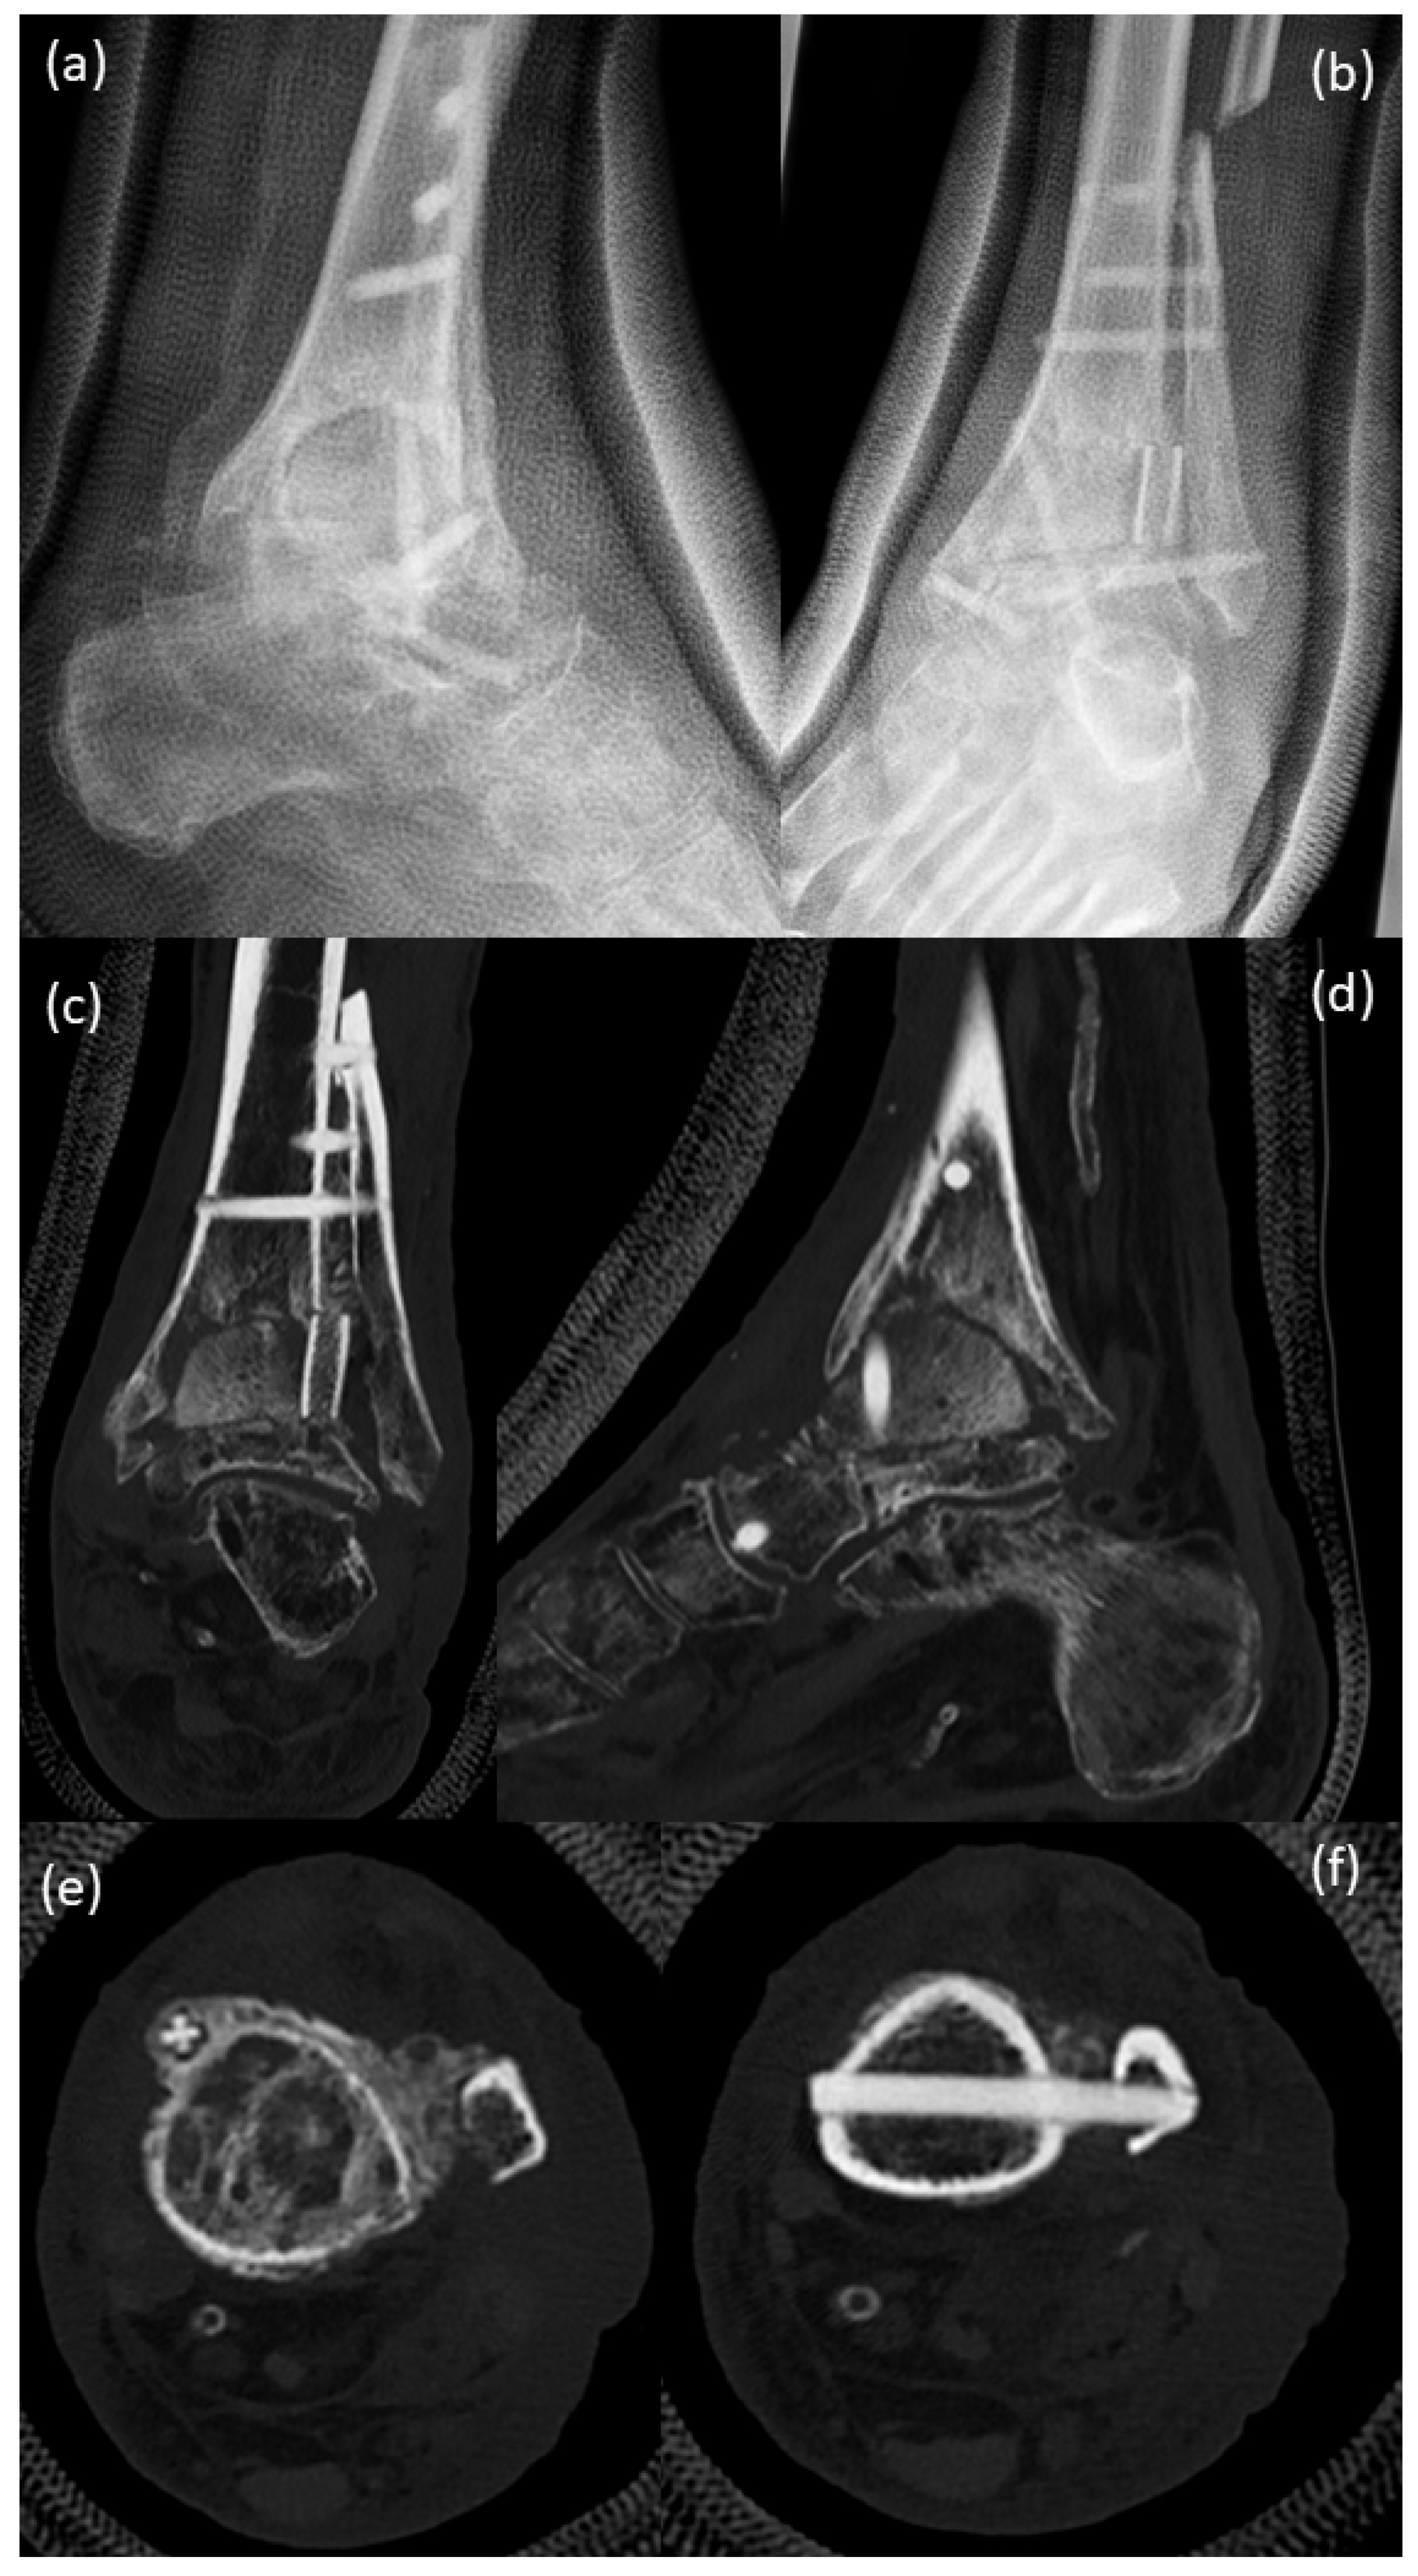

3. Surgical Procedure

4. Postoperative Rehabilitation

5. Results